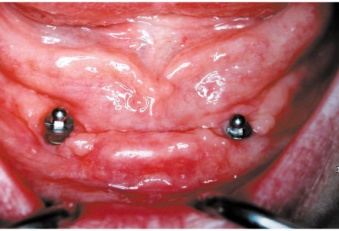

Bezzubá čelist

Kulové attachmenty

Bezzubá čelist je hlavní indikací pro ošetření pomocí implantátů. Zejména celkové zubní náhrady v dolní čelisti mají velice nízkou stabilitu a držení díky velkému úbytku kosti.

S pomocí zubních implantátů můžeme díky různým kotevním systémům (třmeny, kulové hlavy, Locatory) zajistit stabilitu a držení protézy nebo při použití většího počtu implantátů zhotovit pevné náhrady – můstky nalepené nebo našroubované na pevno na implantáty.